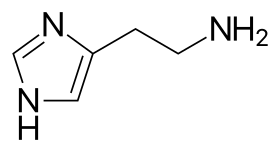

Histamine is an organic nitrogenous compound involved in local immune responses communication, as well as regulating physiological functions in the gut and acting as a neurotransmitter for the brain, spinal cord, and uterus.[3][4] Since histamine was discovered in 1910, it has been considered a local hormone (autocoid) because it lacks the classic endocrine glands to secrete it; however, in recent years, histamine has been recognized as a central neurotransmitter.[5] Histamine is involved in the inflammatory response and has a central role as a mediator of itching.[6] As part of an immune response to foreign pathogens, histamine is produced by basophils and by mast cells found in nearby connective tissues. Histamine increases the permeability of the capillaries to white blood cells and some proteins, to allow them to engage pathogens in the infected tissues.[7] It consists of an imidazole ring attached to an ethylamine chain; under physiological conditions, the amino group of the side-chain is protonated.